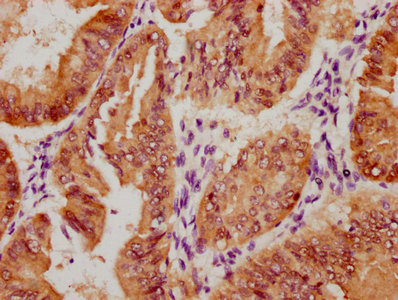

Immunohistochemistry of paraffin-embedded human lung tissue using CSB-PA006593LA01HU at dilution of 1:100